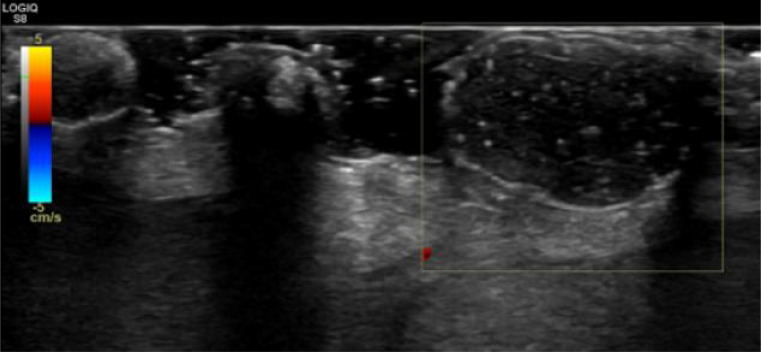

Background: Idiopathic scrotal calcinosis is a rare and benign disease of the scrotal skin that presents as solitary or multiple painless calcified nodules or papules in the absence of systemic disorders of calcium or phosphorus metabolism. Although some theories have been proposed as to the cause of this rare disease, the exact cause remains unknown. In a resource-poor medical setting like Nigeria, a confident diagnosis of this condition can be made with ultrasonography.

Case presentation: This is a case report of a 38-year-old man who presented with recently discharging but longstanding multiple painless scrotal nodules of 22-years duration.

Conclusion: This case illustrates the prompt and accurate diagnosis of idiopathic scrotal calcinosis using an ultrasound, a readily available imaging modality in a low-resource setting.Although histology remains the gold-standard for diagnosing idiopathic scrotal calcinosis following surgical excision, this benign disorder has unique sonographic characteristics that could aid the radiologist in making a confident diagnosis.